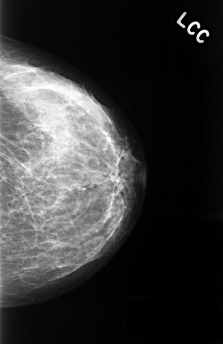

C_0437_1.LEFT_CC

LEFT_CC LINES 4464 PIXELS_PER_LINE 2888 BITS_PER_PIXEL 12 RESOLUTION 50 NON_OVERLAY